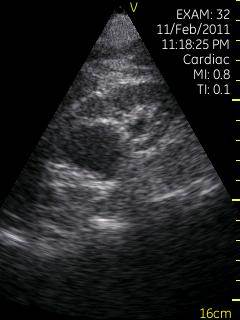

Vscan临床图片 腹部